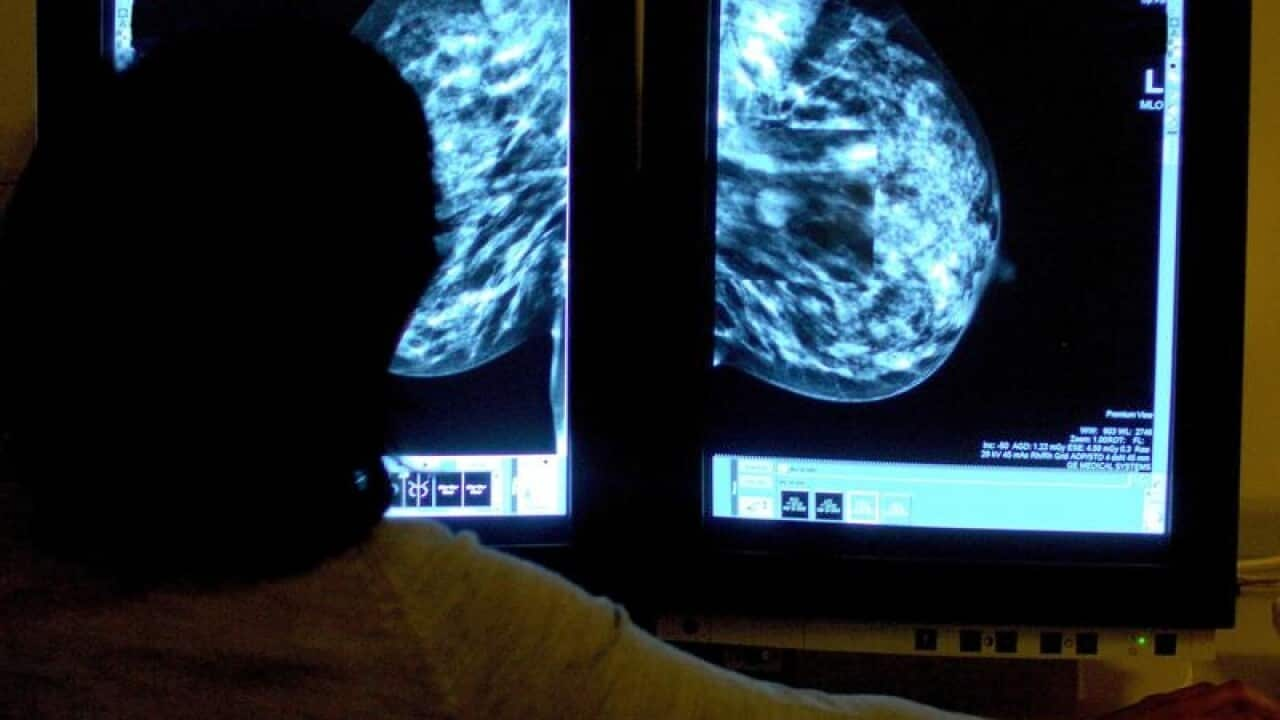

Yearly mammograms starting at age 40 would prevent the most deaths from breast cancer, US researchers report in a challenge to more conservative recommendations that take into account both the harms and the benefits of screening.

The study, led by Elizabeth Arleo, a radiologist specialising in mammography at Weill Cornell Medicine and New York-Presbyterian, found that yearly mammograms between the age of 40 and 80 could cut breast cancer deaths by 40 per cent.

That compares with a reduction of 23 to 31 per cent with current screening recommendations that call for less frequent screening starting at an older age.

"Screening annually starting at age 40 is the best strategy to prevent an early breast cancer death," said Arleo, whose study was published in the journal Cancer.